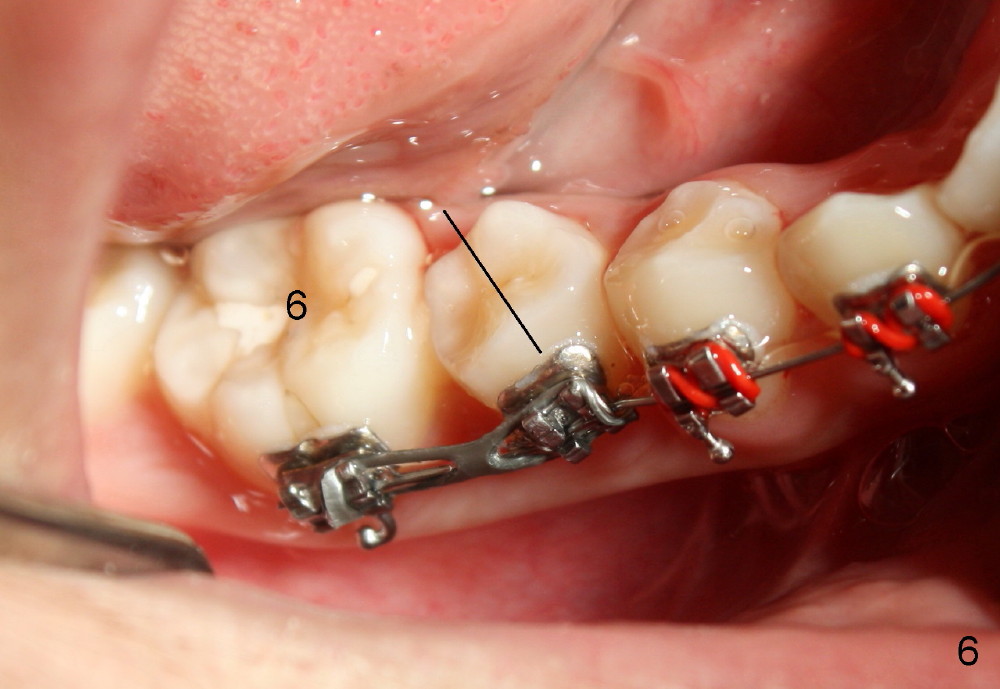

4. Upper 2nd bicuspids (u5s) rotate (Fig.4, 5). Use power chains (Fig.6 different case) to correct rotation quickly to use E space to facilitate u3s eruption (Visit 2)